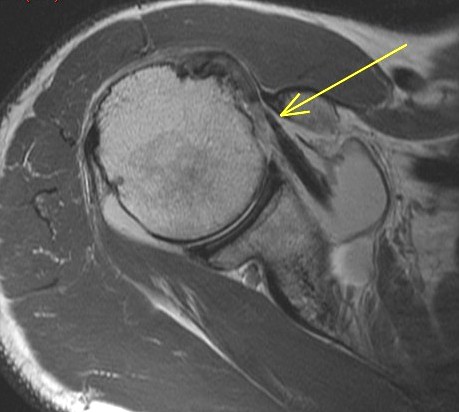

67 y/o with shoulder pain. Shoulder OA. R/O rotator Cuff tear.

The rotator cable is a collagenous thickening of the supraspinatus tendon which acts as a suspension bridge type mechanism strengthening its attachment. In my experience you dont see it in each case but in this case you see it well. Many supraspinatus tears involve the anterior aspect of the tendon and if severe enough can involve the cable and subscapularis tendon. Some consider it extending through the cable to involve the subscap. Biomechanically involvement of the cable can lead to weakness of supraspinatus function whereas if not involved the tear is said be “cresentic” and the patients usually have preserved strength – albeit are in pain. See the enclosed article. Reference article.

Supraspinatus and subscapularis tears involving the anterior rotator cable